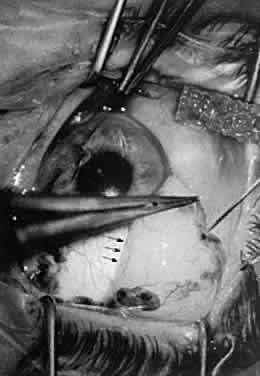

DISSECTING A LAMELLAR CORNEOSCLERAL INCISION

A lamellar corneoscleral incision is useful for surgeons who are working with the anterior segment. This technique may be modified anteriorly for cataract surgery or used more posteriorly for trabeculectomy. The initial vertical incision determines the precise depth of the corneoscleral flap. The length of blade that actually penetrates into the tissue determines this depth. Some knives have a guard that will allow the knife to dissect to a preset depth. However, the depth of dissection can be altered if pressure is applied to the tissue. If the surgeon applies more pressure at the beginning of the incision than he applies at the end of the incision, the depth of the wound will not be uniform. Applying more pressure increases the depth of the incision across the sclera lamellae. It is important to maintain uniform pressure to avoid an incision that is not deep enough. Fixation of the globe is achieved with a toothed forceps. When a guarded blade (with a stop) is used, the blade should be thrust into the tissue fully and the surgeon should pause slightly before the horizontal motion is begun. Pausing slightly allows the blade to settle into the tissue so that the surrounding fibers will be cut evenly. Because the globe is a round object, the blade must be held perpendicular to the globe for the entire length of the incision to ensure uniform depth. At times, maintaining this position requires an awkward hand position for the surgeon unless the blade is held solely between the thumb and fingertips of the second and third fingers. By holding the knife this way, the surgeon may rotate the direction of cutting by rotating the instrument between the fingertips, allowing for a cut of uniform depth. After the tissue is incised to the predetermined depth, lamellar dissection is performed. Various instruments are available to perform a lamellar dissection, such as the no. 64 or 69 Beaver blade, the crescent blade, or the Paufique knife. The initial lamellar dissection is accomplished by first passing the blade vertically into the base of the incision (groove) and then pushing it slightly anteriorly while keeping it in the vertical position. The blade is then oriented in an oblique direction, and the dissection may proceed, with or without tension on the flap (Fig. 39). When the flap being dissected is to be used for cataract surgery (a tunnel incision), dissection with minimal elevation of the flap is advantageous. The advantage of this technique is that elevating or reflecting the flap may deform the tissue and result in dissection at numerous layers. The disadvantage of this technique is that there is no view of the lamellar plane within which the dissection is taking place. However, one generally should be able to see the blade through the sclera tissue. When a watertight seal is desired for cataract surgery, the dissection should proceed anteriorly into the peripheral edge of clear cornea such that the dissecting blade may be seen clearly under the peripheral vascular arcade of the cornea. When a sclera flap is dissected for glaucoma surgery, the lateral aspects of the flap are incised. The flap may be elevated like a hinge to aid the surgeon in visualizing the lamellar dissection plane. The flap must be held centrally so that equal pressure is applied along the length of the lamellar dissection, and care must be taken to keep the lamellar dissection within one surgical plane. The anterior chamber may be entered with the use of the point of a keratome or other surgical blade to cut through the remaining corneal stromal fibers and Descemet's membrane (Fig. 40). This maneuver is best accomplished with the point of a surgical blade that is extremely sharp, so that a diamond or single-use steel knife is recommended.

Fig. 39. A lamellar dissection is performed with a #64 Beaver blade. The blade is oriented in an oblique direction to allow for parallel dissection between the lamellae. Dissection is performed with minimal elevation of the flap. The advantage of this technique is that elevating or reflecting the flap may deform the tissue and result in dissection at numerous layers. The dissection is carried forward until the blade may be seen clearly under the peripheral vascular arcade of the cornea.

Fig. 40. The anterior chamber is entered with the use of a single-use steel keratome.